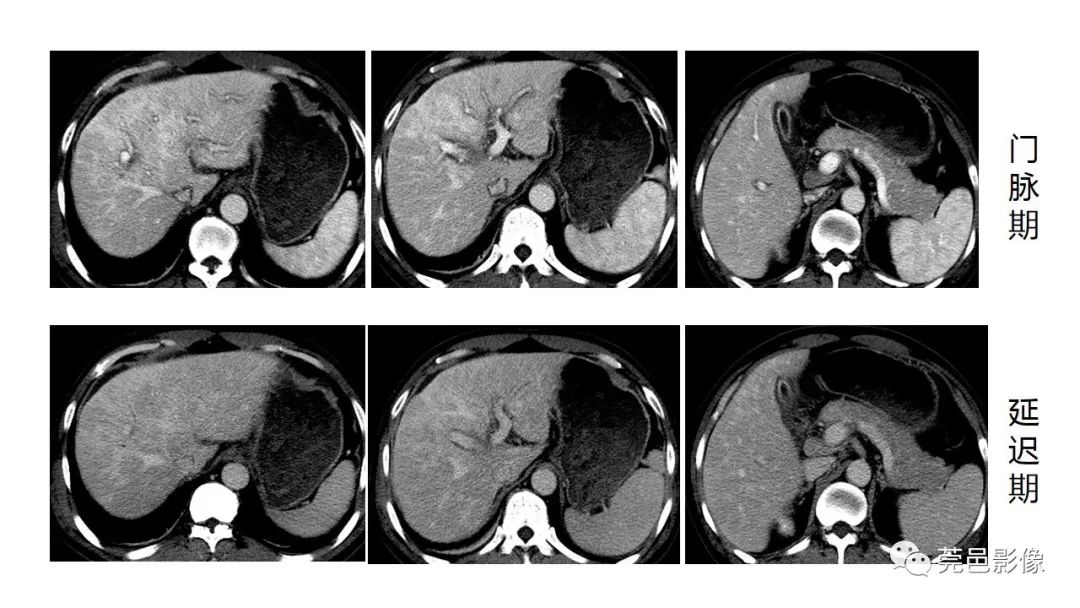

ct增强门脉期

门脉期图像